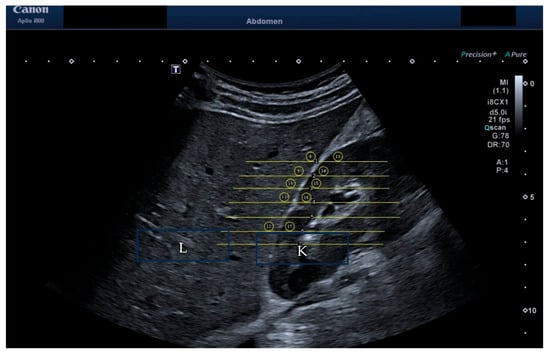

2.2. Depth and ROI Size Analysis

2.3. HRI Versus Attenuation Coefficient